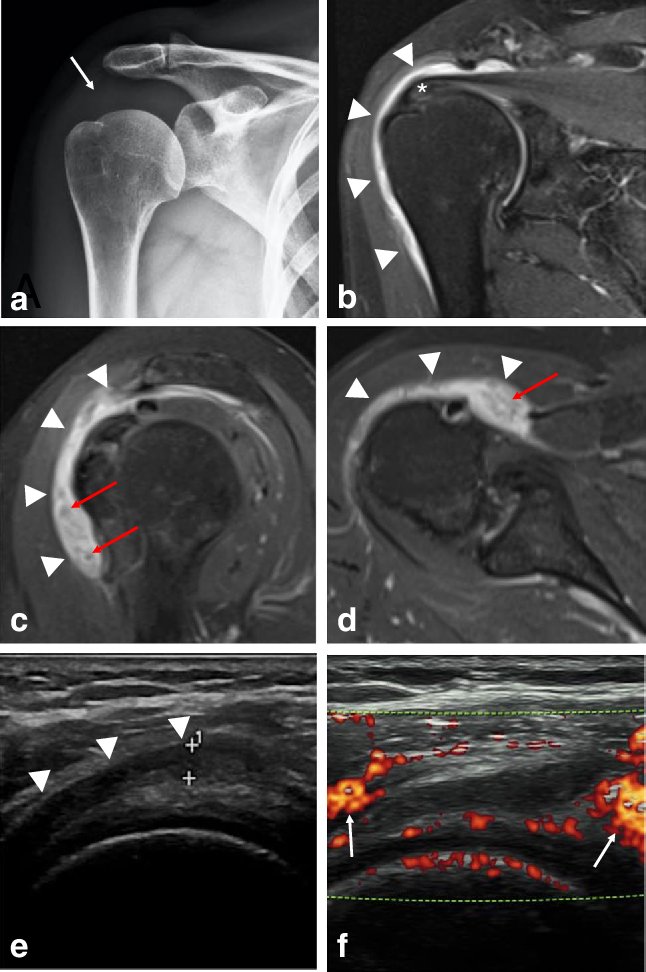

يتم تشخيص إصابة الكتف بعد حقن اللقاح عن طريق الفحص السريري وقد يتطلب إجراء الأشعة الصوتية أو الرنين المغناطيسي لتحديد نوع الإصابة بالكتف

تشمل الإصابة أحد هذه الأمراض:

▪️التهاب مخدة وجراب تحت الأخرم والدالية

▪️تمزق الأوتار والكفة المدورة

▪️التهاب المحفظة اللاصق

▪️التهاب العصب الطرفي